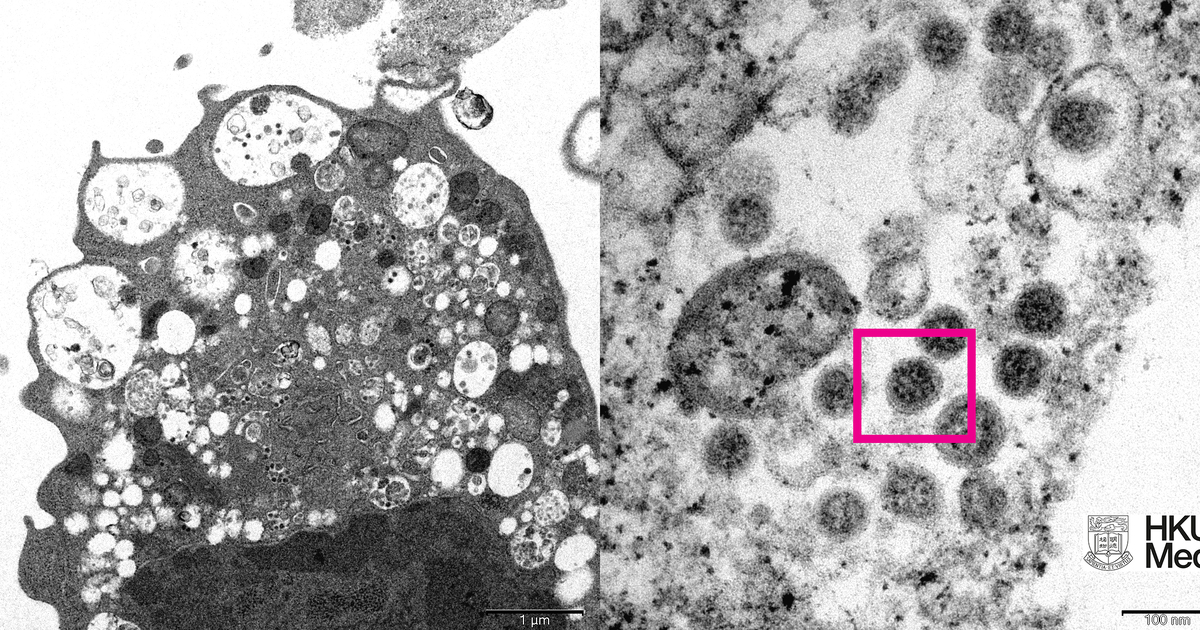

Исследователи сделали электронную микрофотографию клетки почки обезьяны, инфицированной омикрон-штаммом. На ней они увидели повреждения с набухшими везикулами, содержащими вирусные частицы. При сильном увеличении им удалось даже разглядеть скопления характерных сферообразных объектов с шипами в форме короны на их поверхности.